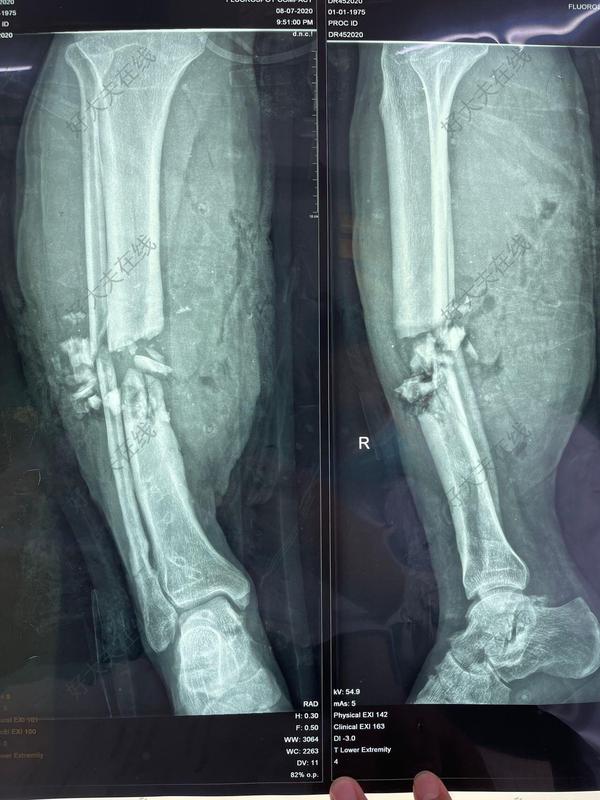

患者55岁男性,高处坠落致右侧小腿肿痛伴活动受限,影像检查显示胫腓骨下端骨折,行机器人辅助下复位及外固定架固定。术前外观连接机器人牵拉并透视调整机械臂,辅助复位安装外固定架六轴机器人辅助下腓骨穿针手术结束

开放性胫腓骨骨折外固定技术

夜骑惊魂,骨折重生的紧急救援55岁的徐某骑电瓶车时不慎摔倒,右下肢着地,伴旋转挤压,当即感右小腿疼痛剧烈,活动受限,伴出血。患者到达医院后,经急诊初步清创处理,东部战区空军医院骨科杨俊生主任详细查体,并迅速完善相关检查,诊断为:右胫腓骨开放性骨折,遂收入骨二科,急诊行手术治疗。开放性骨折受伤后6~8小时内进行手术,能减少后期感染、坏死的风险,但由于患者目前骨折处广泛的软组织损伤,且污染严重,建议先行右小腿清创、牵引复位,外固定术,等待软组织修复,择期更换为内固定手术。取得患者同意后,立即急诊为患者进行右小腿清创、牵引复位,外固定术治疗。健康科普开放性胫腓骨骨折特点为什么要先做外固定,再行内固定手术?清创术后若软组织情况许可,应尽快进行骨骼内固定,但对于有明显骨质丢失、污染或多节段骨折的开放性骨折,外固定支架是有效的选择。外固定器能快速稳定骨折,为软组织修复提供时间,可作为软组织情况欠佳下的临时固定选择。对于损伤严重、感染风险高的患者,也可作为终末固定方式。骨科杨俊生主任讲解道,在创伤骨科的急诊中,开放性骨折出现频率较高,对患者开展治疗工作时,除了要创口清理、固定、使用抗生素等,最主要的环节是进行骨折的固定。开放性骨折的及时固定,能减少骨折端对周围软组织的伤害,以免出现二次污染等情况。开放性骨折的伤口,往往会出现较大的污染,且骨缺损等等,情况严重,因此多选用外固定支架的方式处理。在临床上常常使用到“钉棒系统外固定支架”,由于其操作便捷,对患者的创伤小,且效果较好等优势,因此被广泛运用在急诊患者的损伤救治中,当患者康复到一定程度时,可将其转变为内固定。

【胫腓骨骨折 】 本病例中国科学院望京医院创伤一科提供(术者:CO接骨专家史医师) 【基本资料】患者:女,36岁 本病例胫骨骨折。 【术前X片】 【术中手术图】【术后X片】